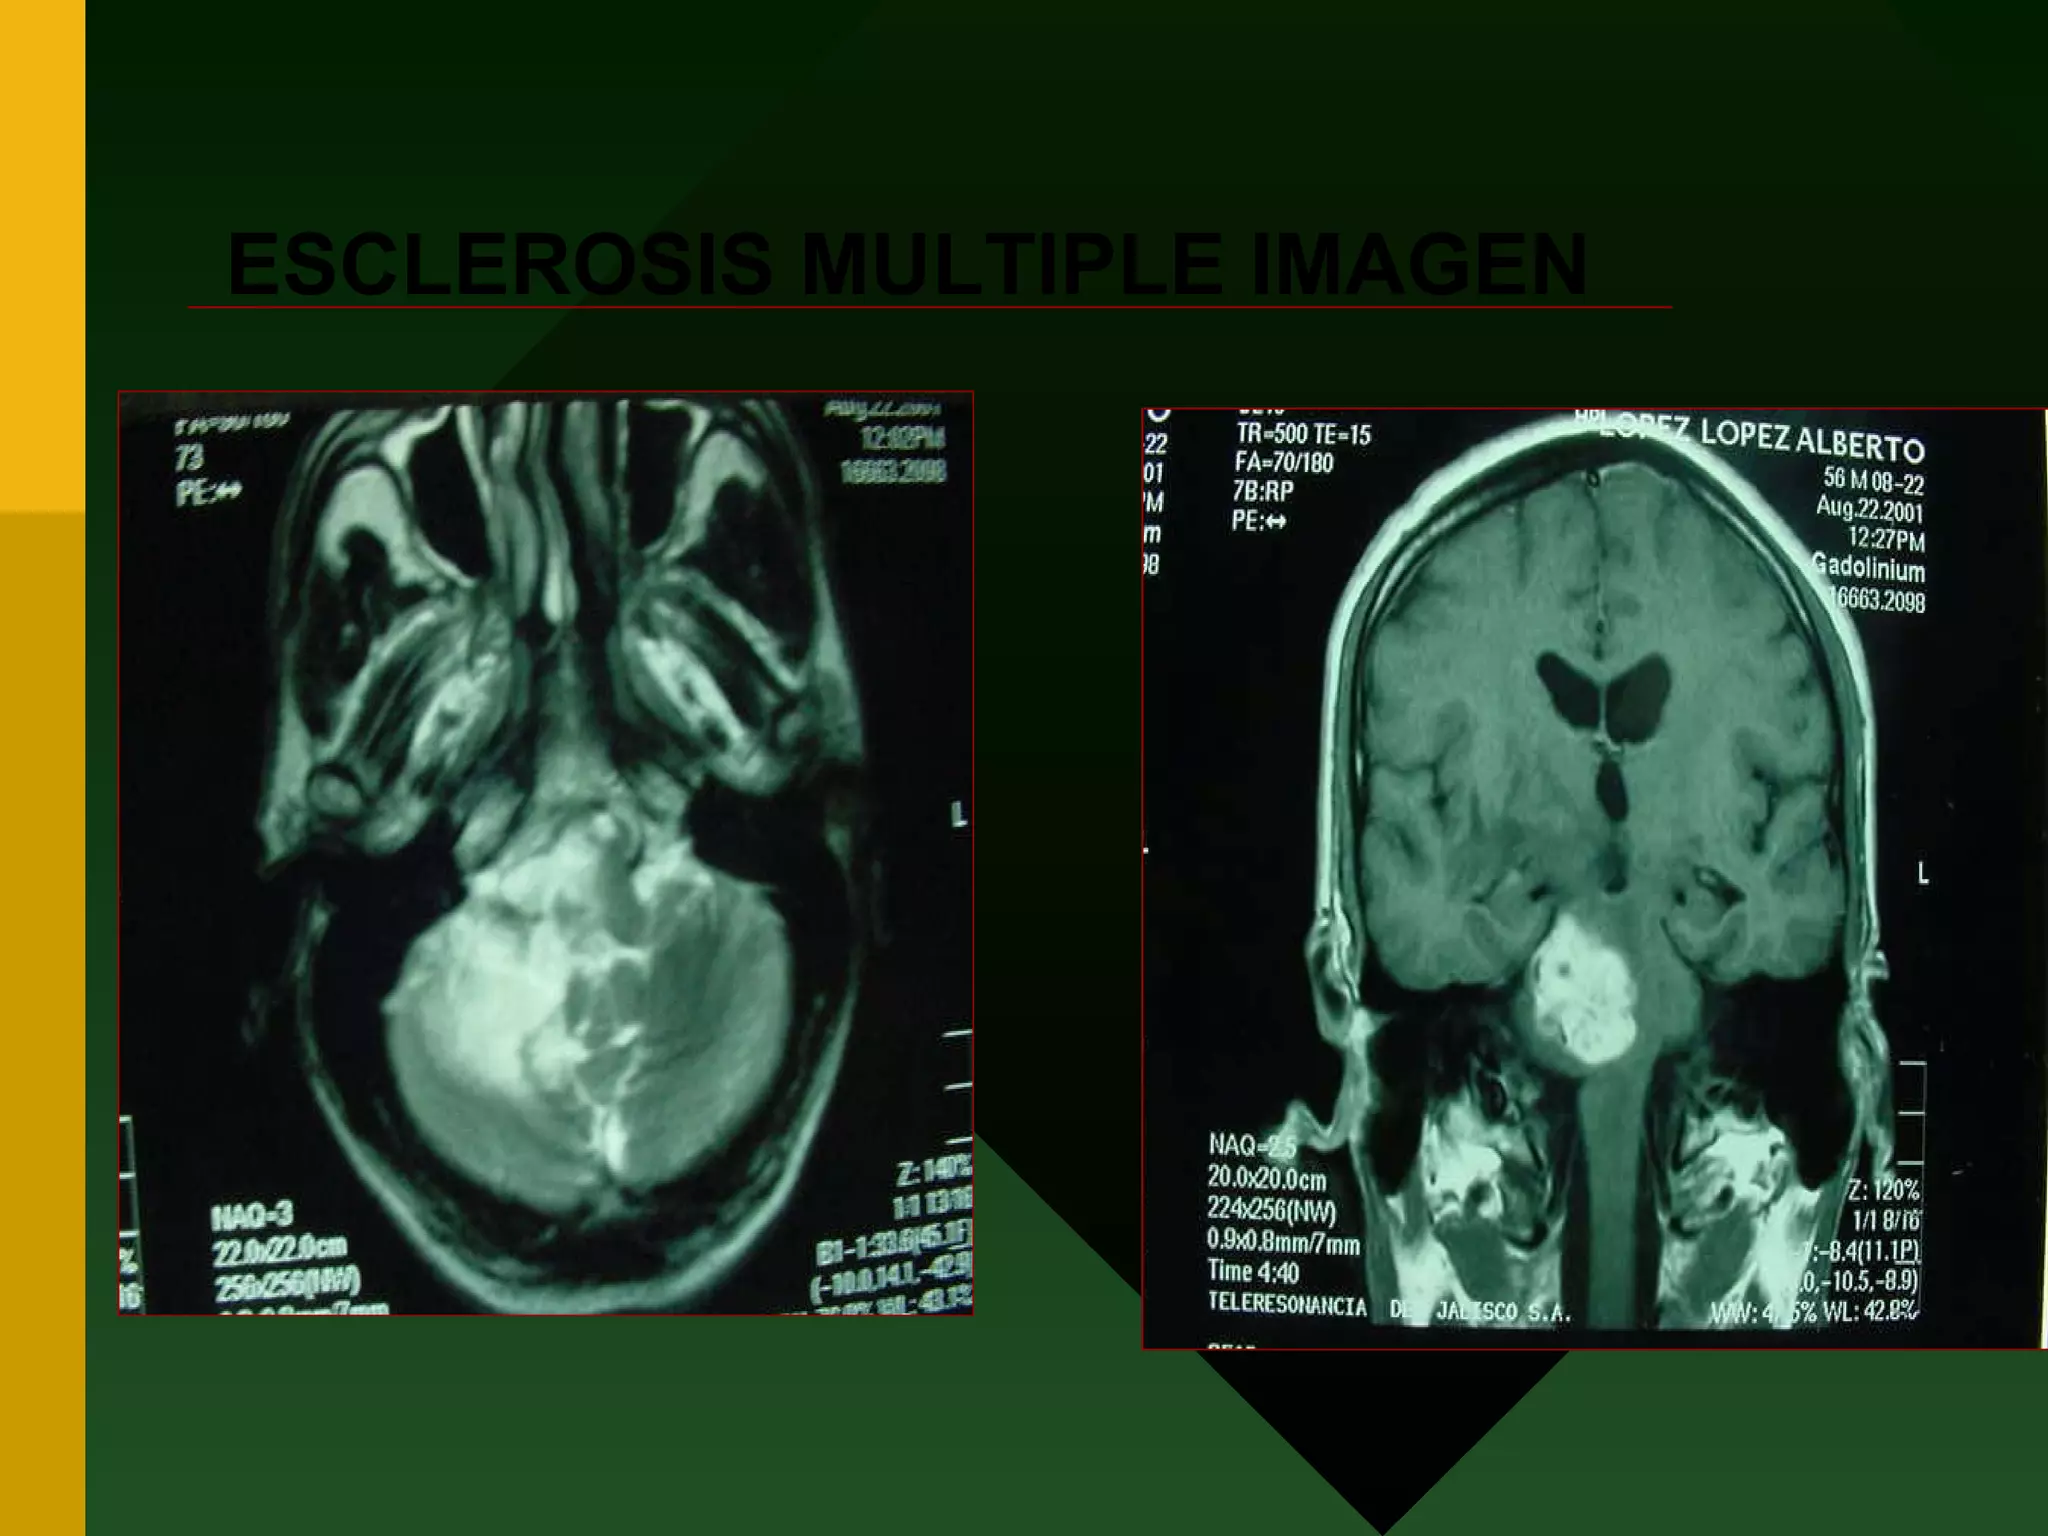

CRITERIOS DIAGNOSTICOS RADIOLOGICOS CRITERIOS DE BARKHOF Y TINTORE TRES DE LAS SIGUIENTES Lesión que refuerce al gadolinio o 9 hiperintensas Al menos tres periventriculares Al menos una en fosa posterior y/o médula Al menos en unión cortico-subcortidal

ESCLEROSIS MULTIPLE IMAGEN

CRITERIOS DIAGNOSTICOS RADIOLOGICOSCRITERIOS DE BARKHOF Y TINTORE TRES DE LAS SIGUIENTES Lesión que refuerce al gadolinio o 9 hiperintensas Al menos tres periventriculares Al menos una en fosa posterior y/o médula Al menos en unión cortico-subcortidal